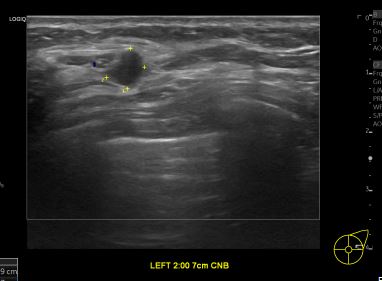

아산유외과개원후 962번째 유방암진단

상기환자 외부검사이상으로 정밀검사위해 내원하신 60대 여성분으로

좌측유방 혹 총조직검사 시행해 유방암 진단되었습니다.